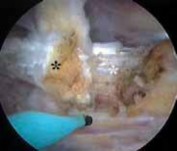

Failure to fully release tendon ■ The iliopsoas tendon forms from the psoas and iliacus muscles. The tendon sometimes

may remain bifid all the way to its insertion on the lesser trochanter. Whether addressing the tendon from the peripheral compartment (

FIG 4A–G

) or from its insertion within the iliopsoas bursa (

FIG 4H,I

), if the tendon looks inordinately small, search for a separate portion of the tendon. Failure to fully release the tendon fibers may result in incomplete resolution of the snapping.

TECHNIQUES A B C D E F G H I ### FIG 4 • A–G. The iliopsoas tendon of the right hip is exposed from the peripheral compartment. A. The initial tendon viewed through a capsular window is fully identified, but is abnormally small. B. This tendon is released with a basket. C. A stump remains. D. This is resected with a shaver. E. Further dissection exposes a more substantial portion of the iliopsoas tendon. F. This is released as well. G. Complete release of the bifid tendon is documented. H,I. Viewing the iliopsoas tendon of a right hip at its insertion on the lesser trochanter within the iliopsoas bursa. H. A bifid iliopsoas tendon is identified with medial (

) and lateral () bands separated by a vessel (

two white asterisks

) coursing perpendicular. I. The lateral band (

black asterisks

) has been released with a flexible RF device, revealing the medial band (

white asterisk

) which subsequently is released. (Courtesy of J. W. Thomas Byrd, MD.)**